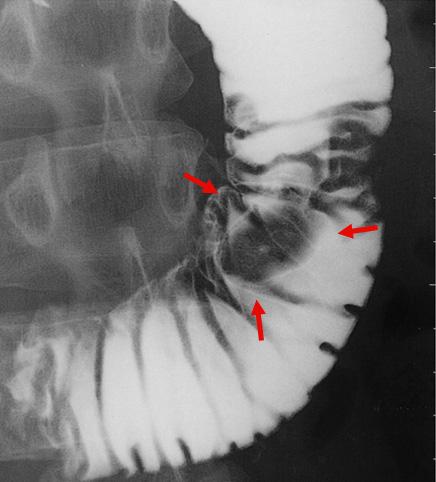

A case of duodenal Brunner's gland hyperplastic polyp which was removed by an endoscopic polypectomy.

Tumor-like lesions/Hyperplastic polyp

Duodenum/Second portion

X-ray

Type 0/I (Ip) Pedunculated type

15 - 19